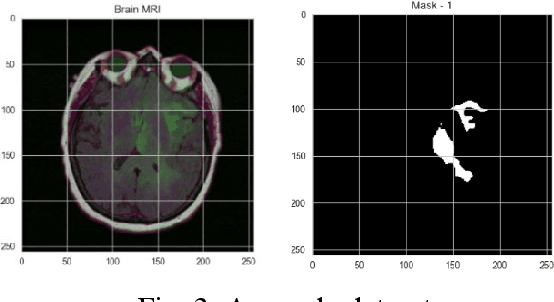

Accurate identification and localisation of brain tumours from medical images remain challenging due to tumour variability and structural complexity. Convolutional Neural Networks (CNNs), particularly ResNet and Unet, have made significant progress in medical image processing, offering robust capabilities for image segmentation. However, limited research has explored their integration with human-computer interaction (HCI) to enhance usability, interpretability, and clinical applicability. This paper introduces ResUnet++, an advanced hybrid model combining ResNet and Unet++, designed to improve tumour detection and localisation while fostering seamless interaction between clinicians and medical imaging systems. ResUnet++ integrates residual blocks in both the downsampling and upsampling phases, ensuring critical image features are preserved. By incorporating HCI principles, the model provides intuitive, real-time feedback, enabling clinicians to visualise and interact with tumour localisation results effectively. This fosters informed decision-making and supports workflow efficiency in clinical settings. We evaluated ResUnet++ on the LGG Segmentation Dataset, achieving a Jaccard Loss of 98.17%. The results demonstrate its strong segmentation performance and potential for real-world applications. By bridging advanced medical imaging techniques with HCI, ResUnet++ offers a foundation for developing interactive diagnostic tools, improving clinician trust, decision accuracy, and patient outcomes, and advancing the integration of AI in healthcare workflows.